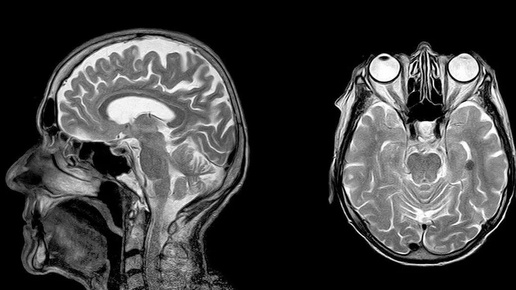

Магнитно-резонансная томография (МРТ), как метод диагностики, все более широко применяется во многих областях медицины. С ее помощью доктора могут проводить прицельное обследование почти всего организма: от головного мозга до голеностопа, от носа до органов малого таза и самых мелких суставов кисти. Еще 10 лет назад на МР-сканировании трудно было в деталях разглядеть сердце или кишечник, но с приходом новых сверхвысокопольных томографов даже кардио-МРТ или виртуальная МР-колоноскопия стали возможными...

Всем привет! Живя в 21 веке еще многие не знают - что же такое мрт и есть ли противопоказания для положения данного исследования. Так давайте с Вами в этом разберемся . Мрт - это магнитно-резонансная томография, где выстраивается магнитное поле для исследования. В отличие от Кт- компьютерной томографии , здесь нет облучения. МРТ наиболее информативное исследование , а также и самый безопасный метод диагностики. Процесс заключается в помещении пациента в тоннель томографа, где и создаются снимки необходимых органов...